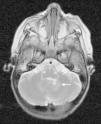

La histiocitosis de células de Langerhans (HCL) es una enfermedad rara caracterizada por la acumulación en los tejidos de células dendríticas anómalas similares a las células de Langerhans. La presentación clínica varía desde la aparición de una lesión ósea única hasta la afectación multisistémica. La implicación del sistema nervioso central (SNC), manifestada como diabetes insípida secundaria a afectación hipofisaria, es conocida desde la descripción original de la enfermedad. En la actualidad, se diferencian 2 tipos de lesiones del SNC: las lesiones seudotumorales, con infiltración por las células de Langerhans, cuya manifestación más frecuente es la infiltración hipofisaria, y otras, de más reciente descripción, las lesiones neurodegenerativas del SNC, asociadas a deterioro neurológico, que constituyen una complicación de la enfermedad de causa discutida. Nuestro objetivo es describir las manifestaciones radiológicas de la HCL en el SNC en los pacientes pediátricos.

Langerhans cell histiocytosis (LCH) is a rare disease characterized by the accumulation within tissues of anomalous dendritic cells similar to Langerhans cells. The clinical presentation varies, ranging from the appearance of a single bone lesion to multisystemic involvement. Central nervous system (CNS) involvement, manifesting as diabetes insipidus secondary to pituitary involvement, has been known since the original description of the disease. Two types of CNS lesions are currently differentiated. The first, pseudotumoral lesions with infiltration by Langerhans cells, most commonly manifests as pituitary infiltration. The second, described more recently, consists of neurodegenerative lesions of the CNS associated with neurologic deterioration. This second type of lesion constitutes a complication of the disease; however, there is no consensus about the cause of this complication. Our objective was to describe the radiologic manifestations of LCH in the CNS in pediatric patients.